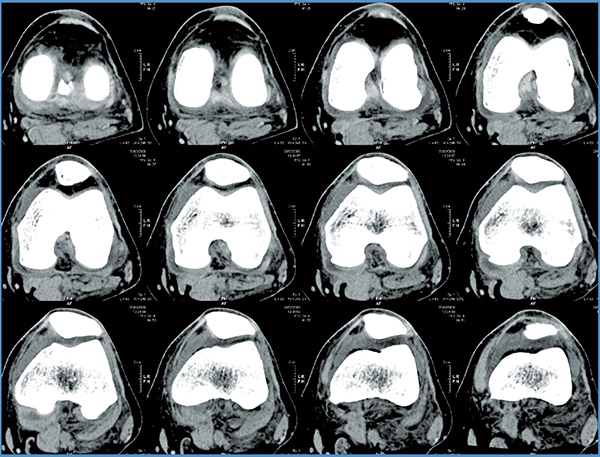

Total Hip Replacement

- Mako Robotic-Arm Assisted Total Hip replacement is a surgical procedure intended for patients who suffer from non-inflammatory or inflammatory degenerative joint disease (DJD). Some forms of DJD include osteoarthritis (OA), post-traumatic arthritis, rheumatoid arthritis (RA), avascular necrosis (AVN) and hip dysplasia.

Step 1. Hip CT Scan

Step 2. Hip Personalized Planning